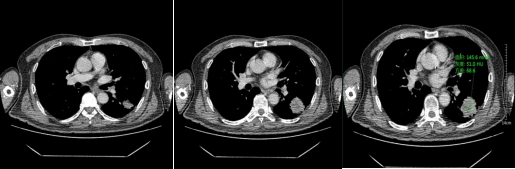

动脉期

静脉期